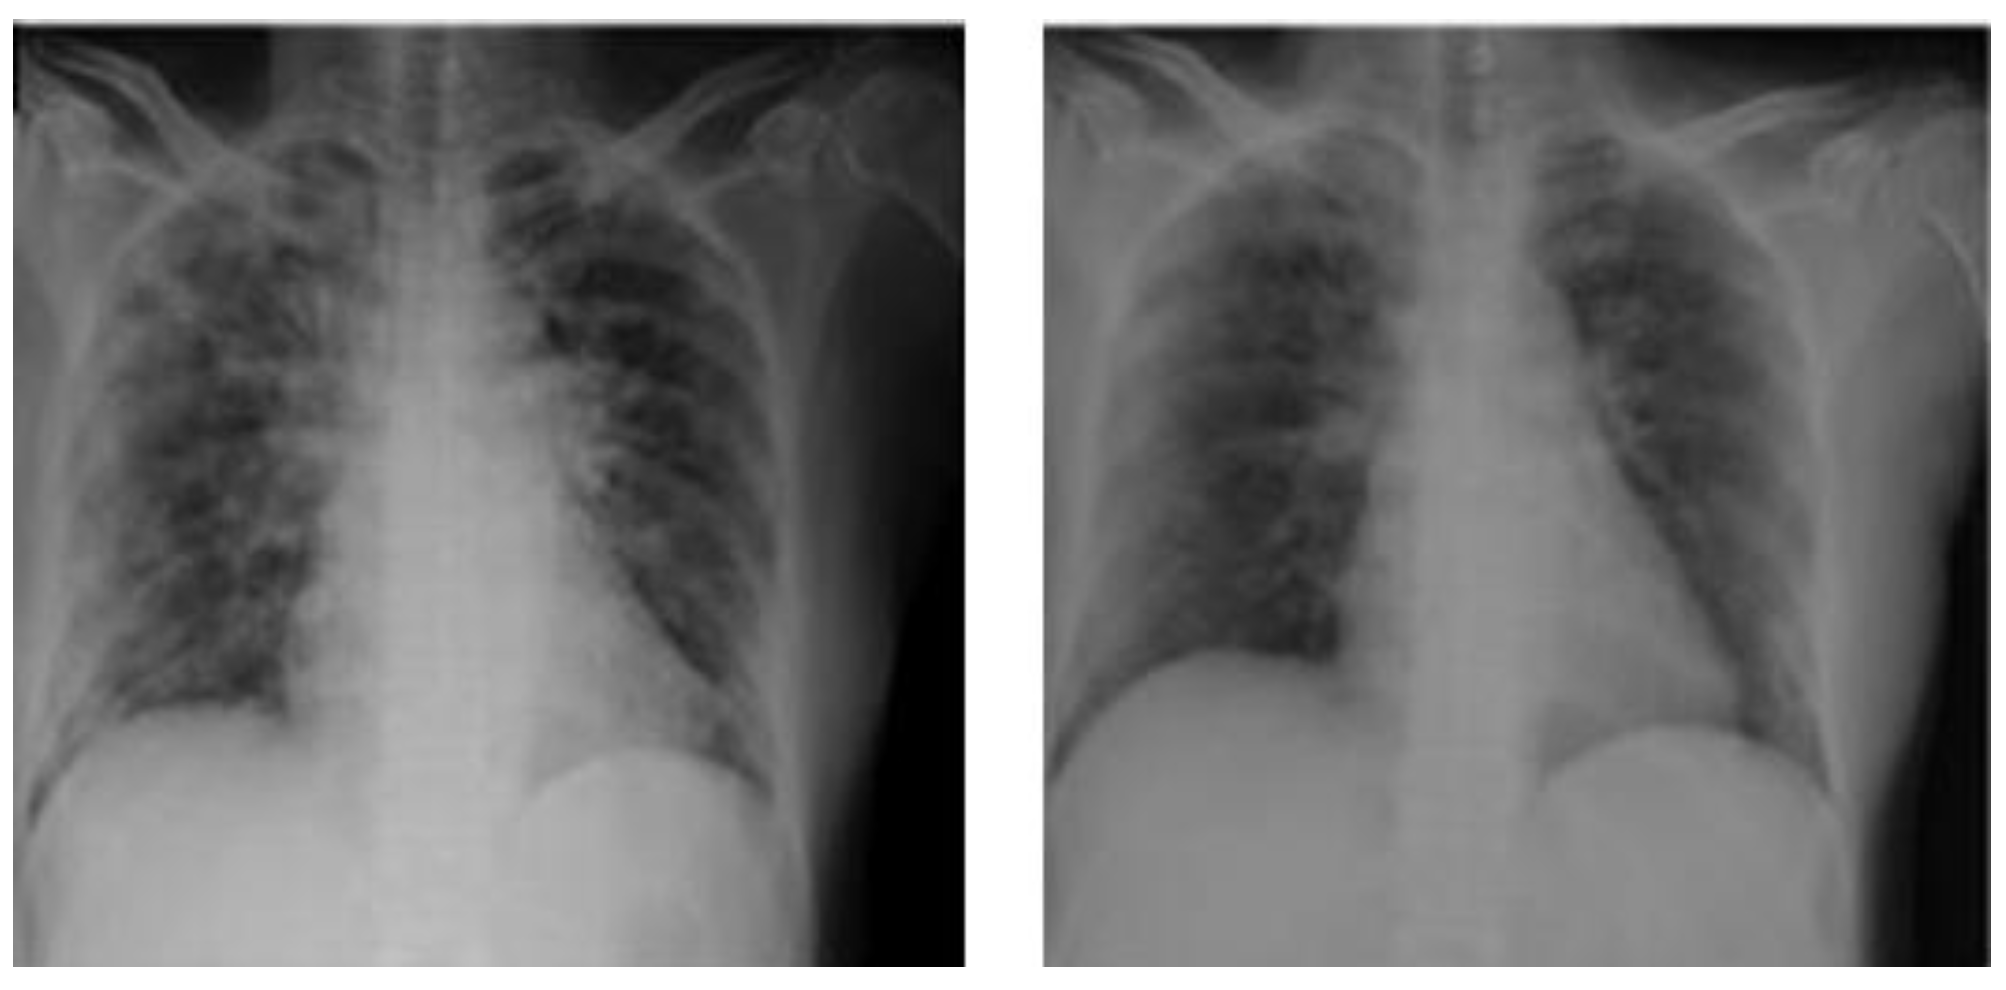

| (Horry et al., 2021) [6] | X-ray-image-based COVID-19 detection | Convolutional neural network models | VGG, Inception, Xception, and Resnet | Patchy infiltration or opacities | Publicly available | X-ray images | 200 × normal vs.100 × COVID-19100 × pneumonia | Both VGG16 and VGG19 classifiers provided good results within the experimental constraints of the small number of X-ray images. Around 80% for both recalls, and simpler networks such as VGG19 performs relatively better with up to 83% precision. |